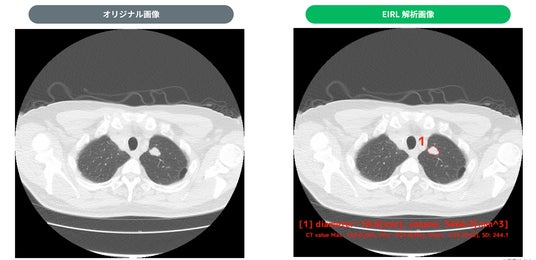

・検出例

1. 18.6mm 充実型